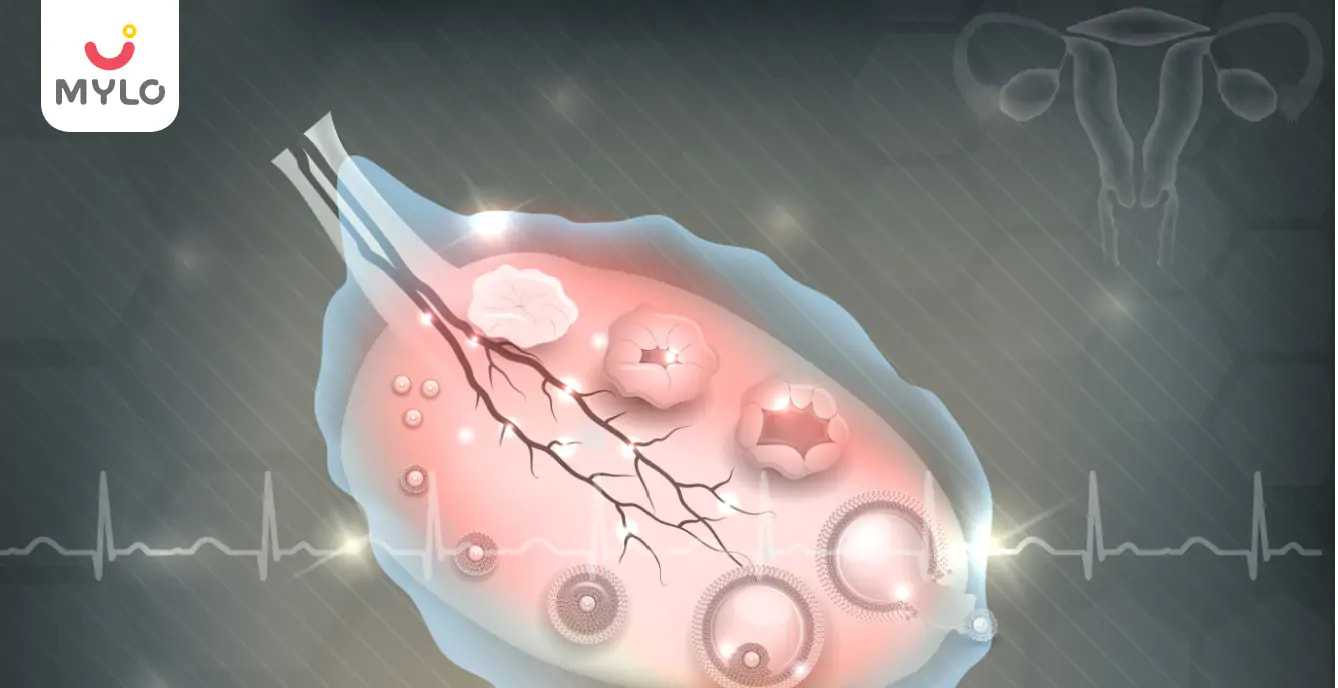

Ovulation refers to the process during which the female body releases an egg. Disorders or problems with the ovulation process can cause difficulty in conceiving and may even lead to infertility.

Common Ovulation Disorders in Women

Some types of ovulation disorders are:

1. Polycystic ovarian syndrome

A woman with polycystic ovarian syndrome (PCOS) has enlarged ovaries, often with small, fluid-filled cysts on them. It can lead to a hormonal imbalance which may disrupt the ovulation process.

Article continues below advertisment

Other symptoms of PCOS include: insulin resistance, obesity, abnormal hair growth, and acne.

PCOS is the leading cause of infertility in women.

2. Hypothalamic dysfunction

Hypothalamic dysfunction occurs when the production of the FSH and LH hormones is disrupted. These are the hormones that stimulate ovulation. This can affect the menstrual cycle.

Irregular menstrual cycles and amenorrhea, which means not menstruating at all, are common.

Causes of hypothalamic dysfunction include: excessive physical or emotional stress, extremely high or low body weight, substantial weight gains or losses, extreme exercise or tumours on the hypothalamus.

3. Premature ovarian insufficiency

This is when egg production stops prematurely because of a reduction in oestrogen levels.

It can be caused due to an autoimmune disease, genetic anomalies, or environmental toxins.

It typically affects women before the age of 40 years.

4. Hyperprolactinemia, or excess prolactin

In certain situations, such as the use of specific medication or an abnormality in the pituitary gland, which is responsible for the production of hormones in the body, women can produce excessive amounts of prolactin. This, in return, can cause a reduction in the production of oestrogen.

Excess prolactin is an uncommon cause of ovulatory dysfunction in women.